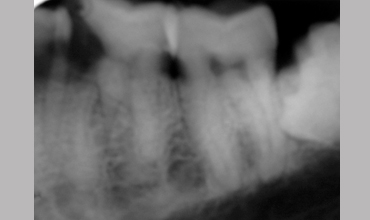

Management Of Radix Entomolaris In Mandibular First Molar